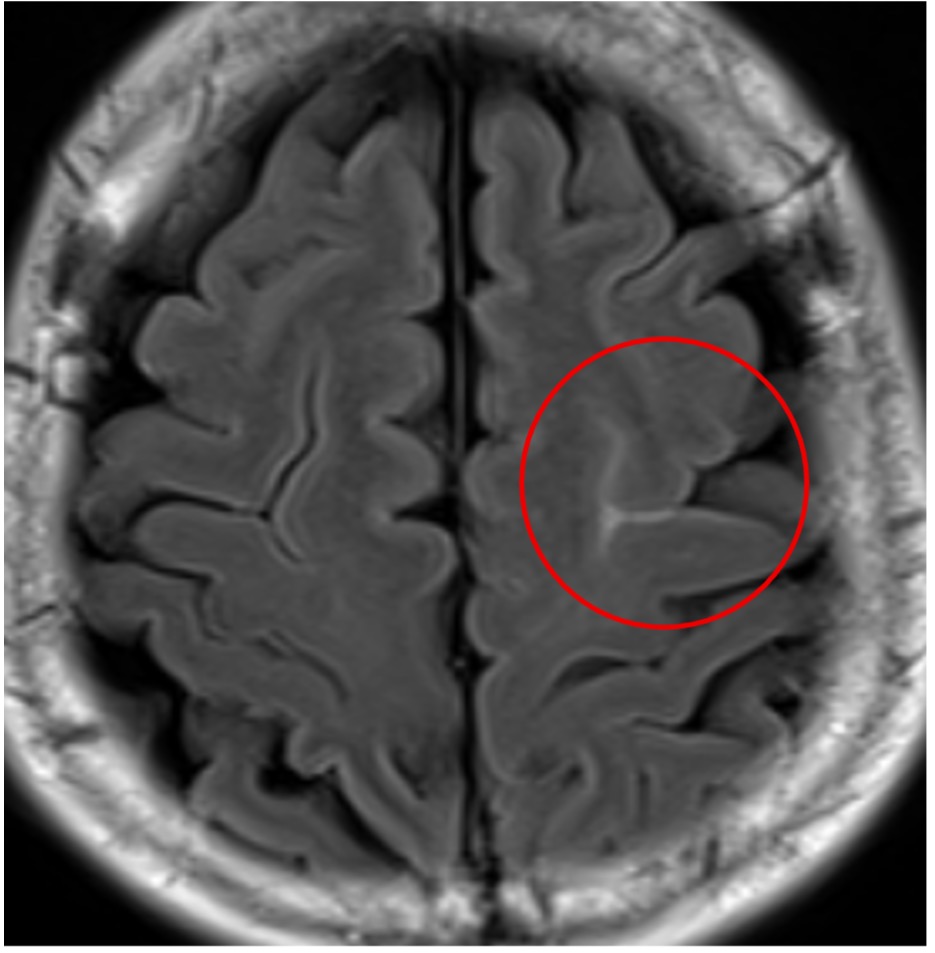

円蓋部(えんがいぶ)くも膜下出血

頭部MRI:白く映っているところがくも膜下出血

脳の表面に少量の円蓋部(えんがいぶ)くも膜下出血

また、少し変わったくも膜下出血もあります。脳動脈瘤が破綻すると脳底部を中心に出血が広がりますが、脳の円蓋部(えんがいぶ)とよばれる脳の表面に少量のくも膜下出血が起こることがあります。この場合は脳動脈瘤の破裂が原因のことはまずありません。円蓋部くも膜下出血で最も多いのは外傷性です。問題となるのは非外傷性で原因が特定できないこともあります。高齢者の場合はアミロイド血管症、若年者で可逆性脳血管攣縮症候群(RCVS)が原因として多いようです。そのほかに脳静脈洞血栓症細菌性心内膜炎(末梢の微小な感染性脳動脈瘤の破綻)、脳動静脈奇形、動脈解離、血管炎などが原因のことがありより詳しい検査が必要となることがあります。見逃されやすい画像所見であり注意が必要です。